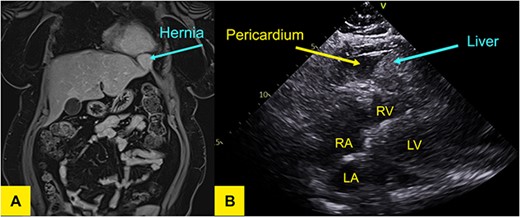

An echocardiogram revealed moderate loculated pericardial effusion and an echo dense mass within the pericardium measuring 4.2 × 4.3 cm creating mass effect on the right ventricular free wall. The defect was better appreciated on a subsequent MRI of the liver (Fig. 1A).

(A) T1-weighted MR of the liver in coronal plane showing a wide neck hernia at the anterolateral aspect of left hemidiaphragm that contains liver tissue and bulges outside the liver contour. No signal/enhancement abnormality. (B) Transthoracic echocardiogram demonstrating liver in pericardium adjacent to left ventricle.